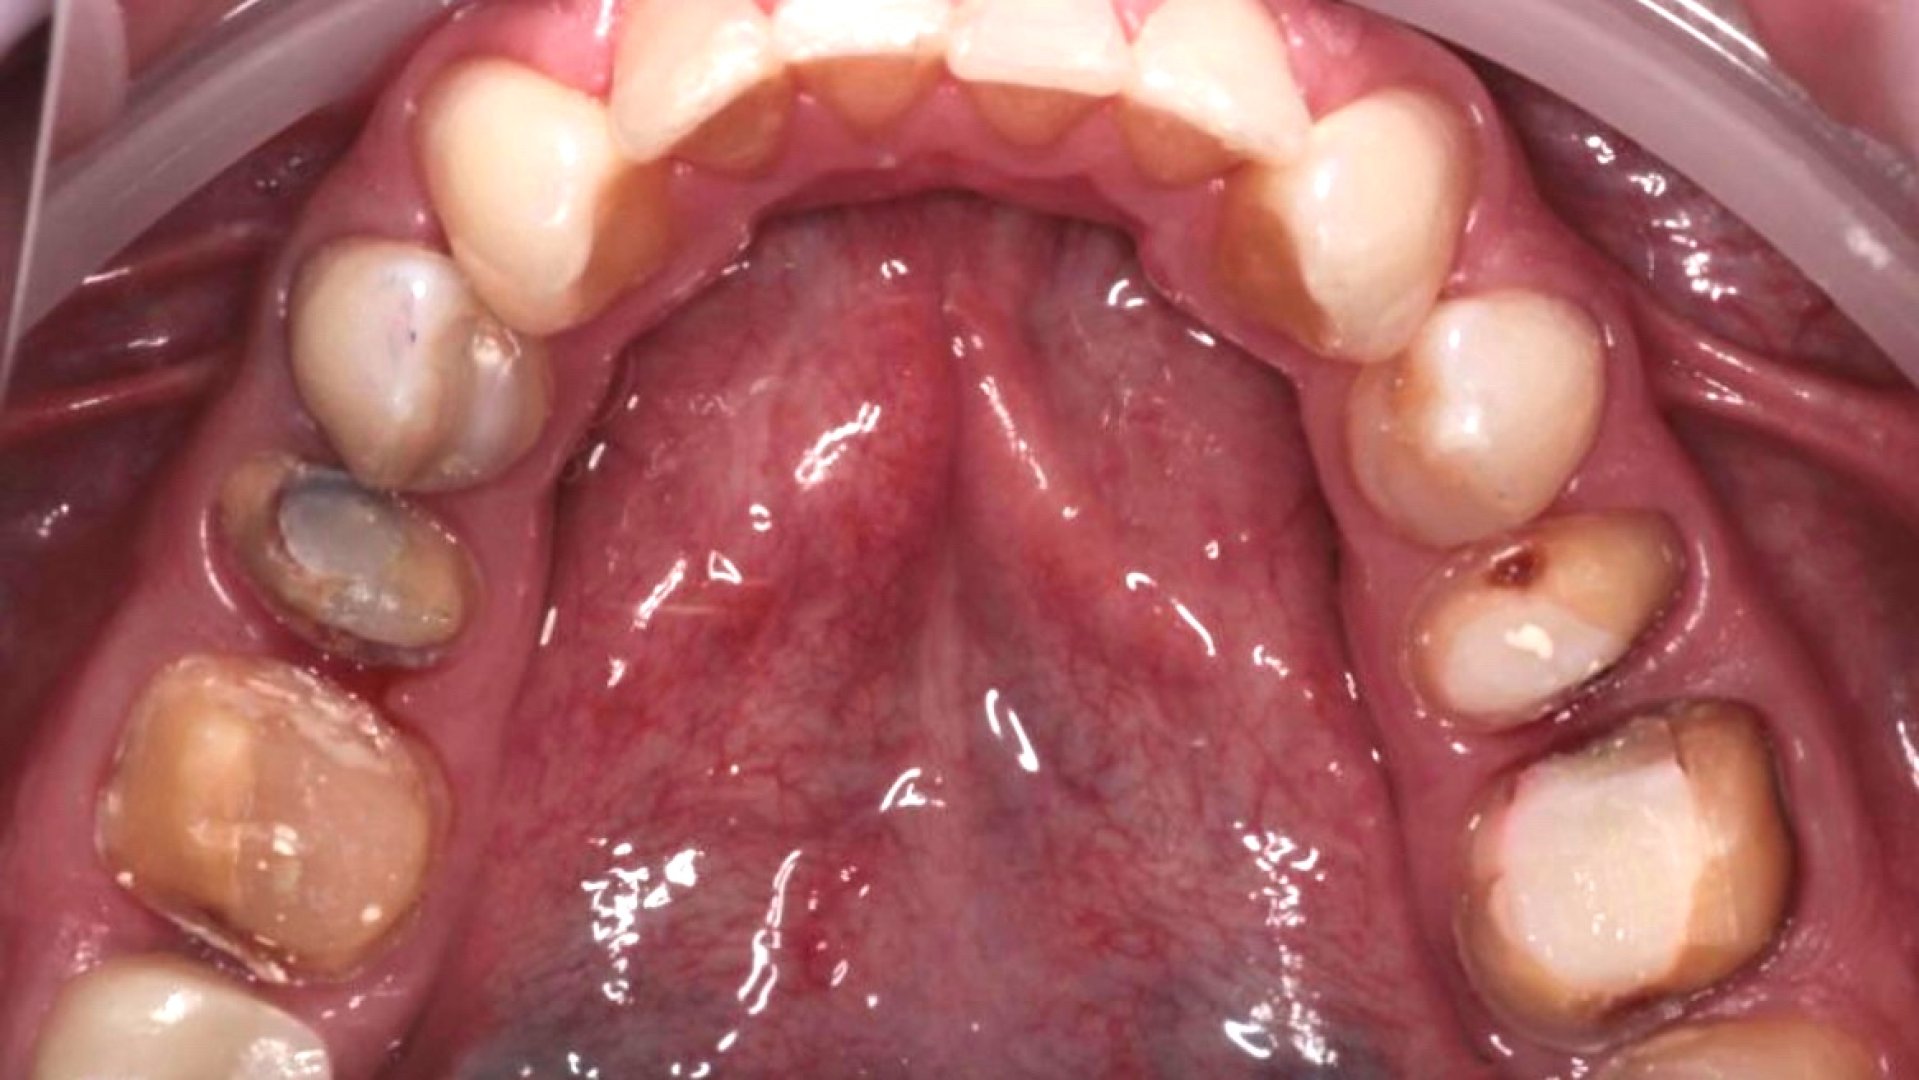

После

Циркониевые коронки на жевательные зубы. 3.5-3.6, 4.5-4.6_after